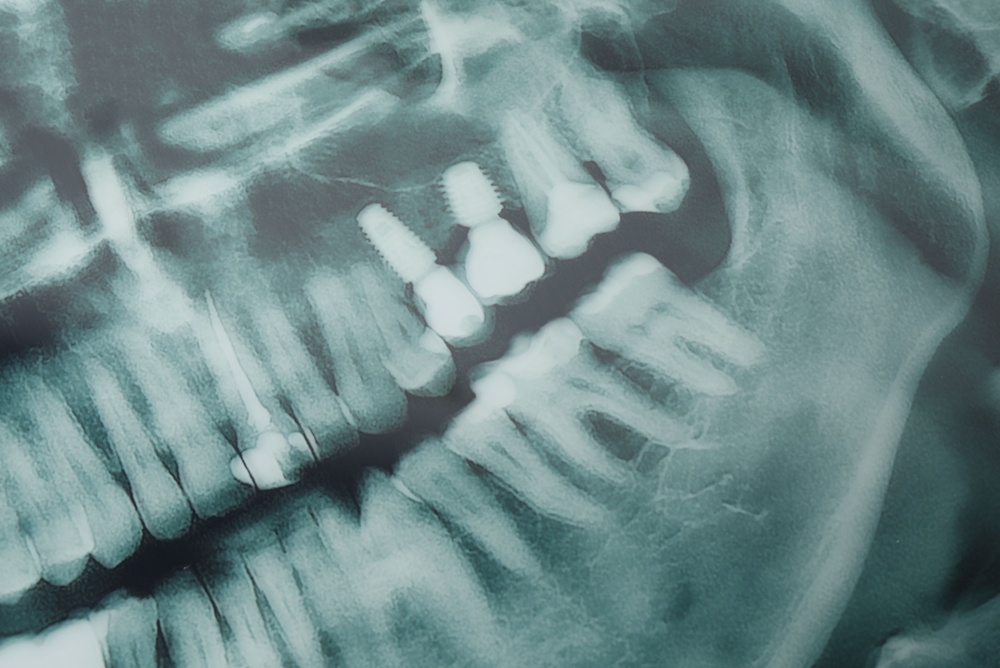

Endosteal (root-form) implants

These are the most common implants. A titanium screw is placed into the jawbone to act like a tooth root. After healing, an abutment and crown attach to the implant. Used for single teeth, bridges, or to support full-arch prostheses.

Implants rely on osseointegration — the bone grows tightly around the implant’s surface. Main parts: the implant (root), the abutment (connector), and the crown/bridge/prosthesis (the visible tooth). Typical timeline: consult and scans, implant placement, healing (often 3–6 months), then placement of the final restoration.